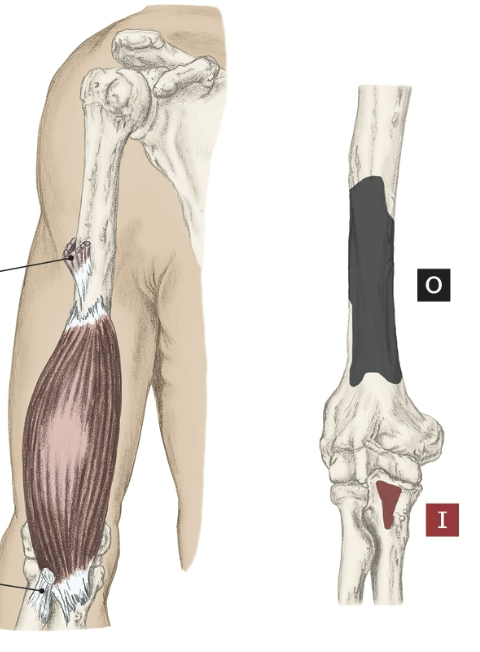

Action of the Brachialis

Elbow flexion

Origin of the Brachialis

Distal half of the anterior surface of the humerus

Insertion of the Brachialis

Coronoid process of the ulna and tuberosity.

Nerve that the Brachialis innervates

Musculocutaneous